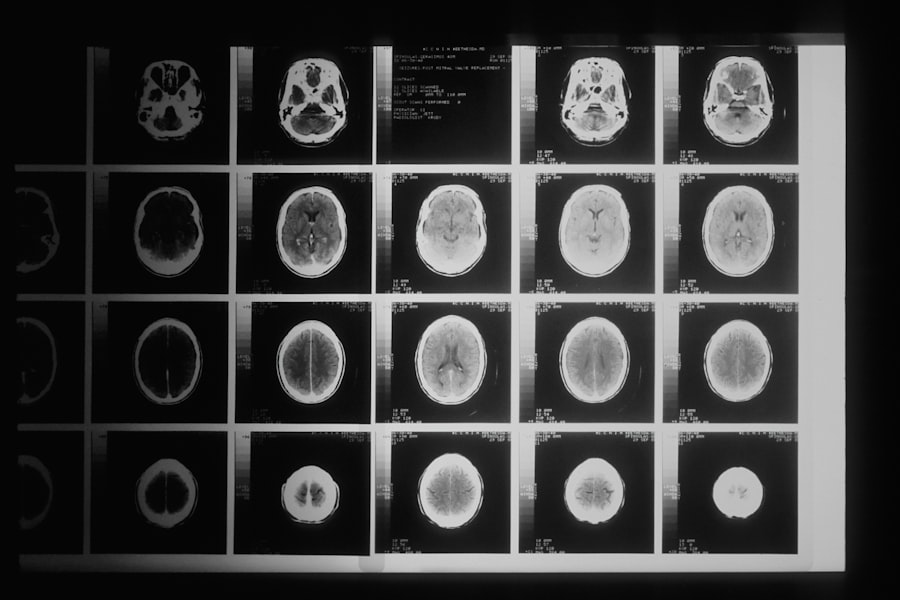

Le cancer du cerveau

Le cancer du cerveau lui-même peut également affecter directement les fonctions cognitives. Les tumeurs cérébrales peuvent perturber le fonctionnement normal du cerveau et entraîner des problèmes de mémoire, de concentration et de prise de décision.